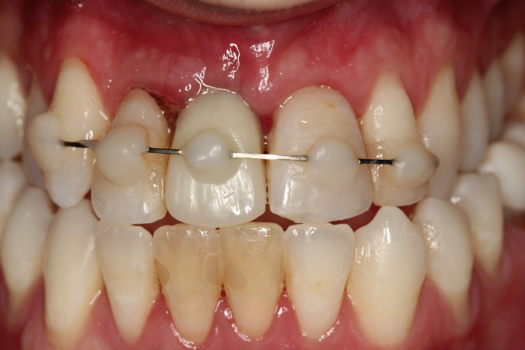

Case 3. TRAUMA: SINGLE Central INCISOR-GUIDED Smile

A 23-year-old man reported to the dental practice on January 3. Apparently, while on vacation and celebrating the New Year, the patient experienced a loss of equilibrium and found himself horizontal in the crosswalk. When surveying the damages, his friends noticed he was missing tooth No. 8. Those who were involved were not able to find the missing maxillary central incisor. The young man was eventually seen about 3 days after the trauma. A CBCT radiograph, study models, and photographs were collected, and teeth Nos. 6 through 10 were immobilized with composite and 20 x 20 orthodontic wire (Figure 14). The CBCT and photos were emailed to the dental laboratory, and the analog intraoral impression with a centric occlusion bite registration was sent via ground transportation. Due to the nature of the trauma, the laboratory and the author expeditiously converted the analog diagnostics and merged all the patient's data sets to develop the plan. Based on the 3D data sets, the laboratory and the dentist were able to accurately assess the volume of bone and soft tissue remaining after the trauma. The volume was still intact and soft tissue was plentiful (Figure 15 and Figure 16).

Fig 14. Immobilization splint placed 3 days after trauma.

Figure 14

Figure 25

Fig 26. Postoperative at 2 weeks.

Figure 26

Fig 27. Postoperative at 6 weeks.